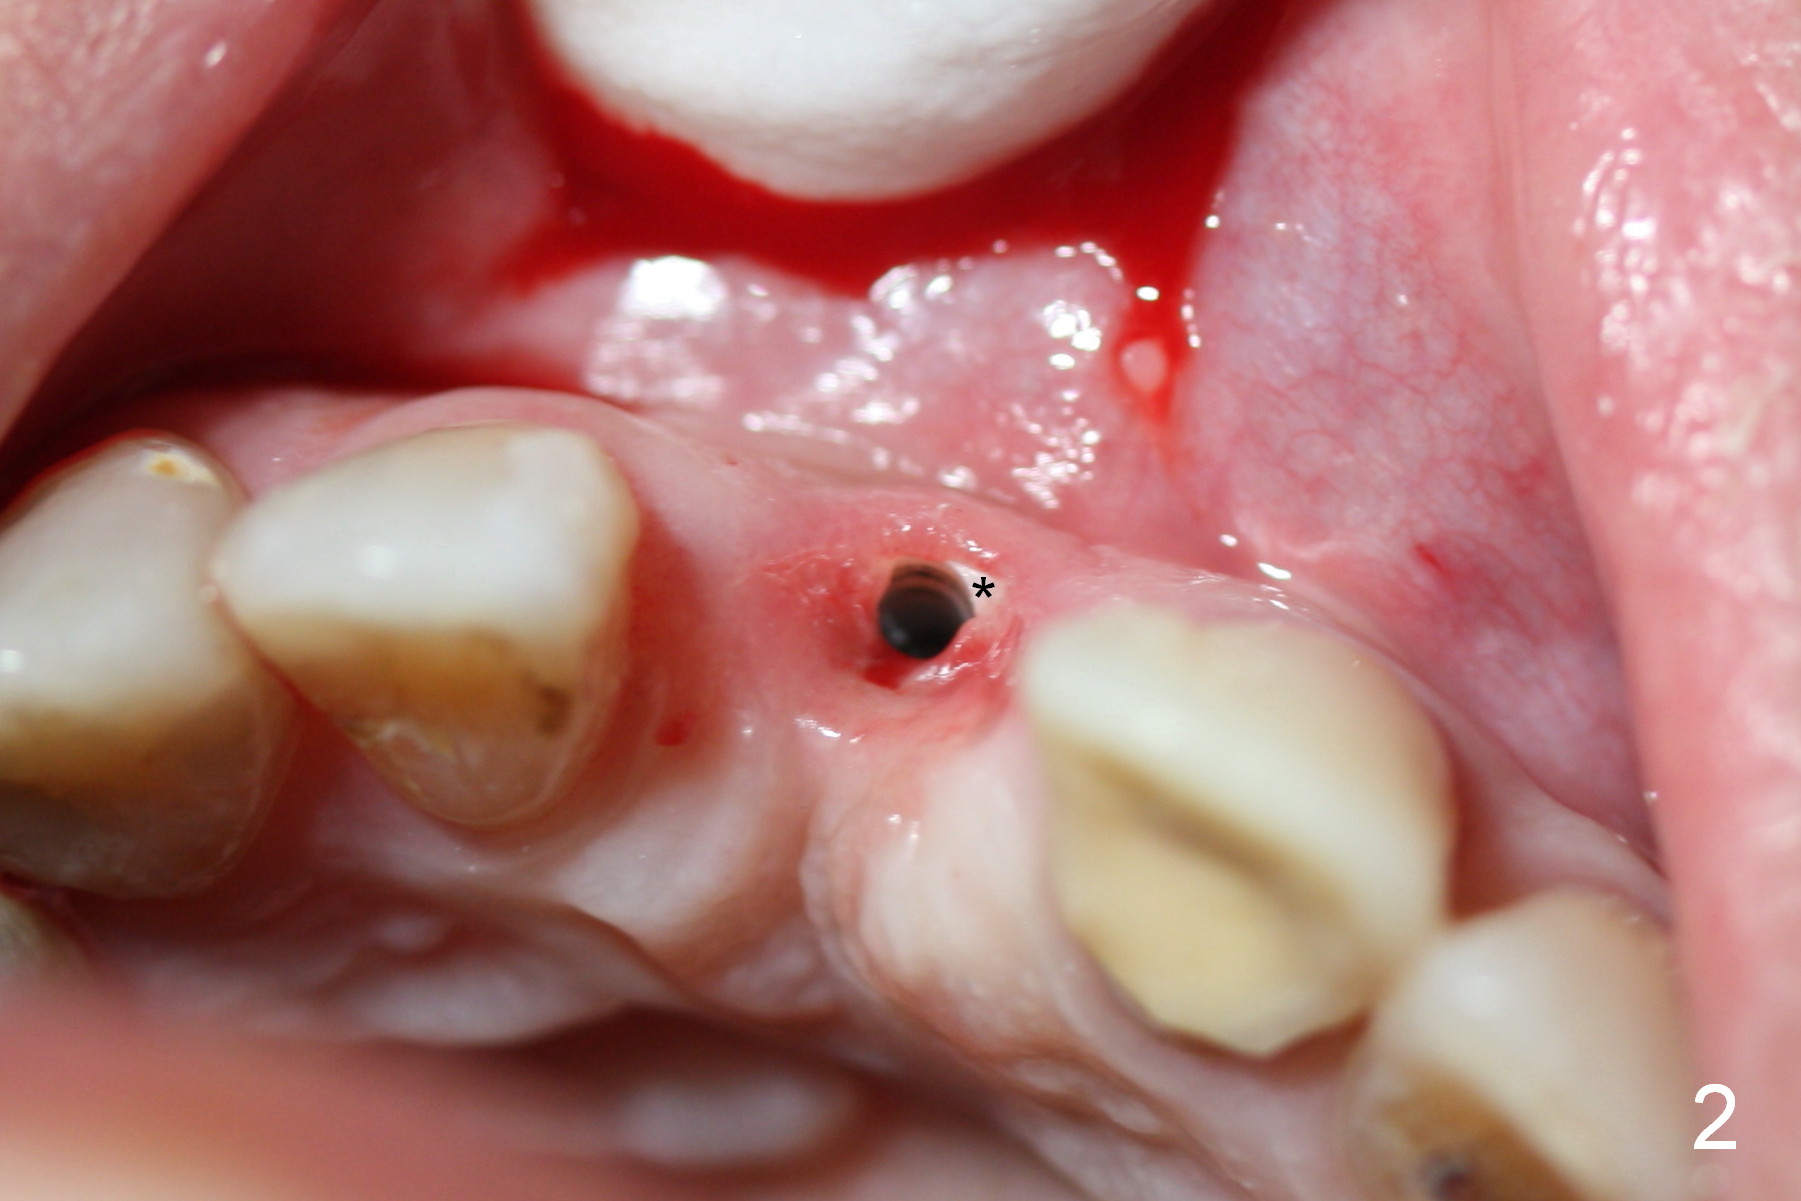

The patient returns for Zirconium abutment retrieval 1 month post its fracture.  When the provisional is removed, the gingival pontic morphology remains (Fig.2).  There is no problem to remove the abutment screw (Fig.1 with its driver), whereas it is difficult to remove the remaining abutment (Fig.2 *) due to limited access.  When the access improves by incision (Fig.3), buccal implant thread exposure is confirmed and the fractured abutment (*) is to be removed easily.  A 15° angled abutment (A) corrects the angulation, but not the position (Fig.4,5, compare to Fig.1 with a driver in place).  After being trimmed, the labial contour of the abutment is equivalent to that of #9 (Fig.6,7), but the margin is higher.  Using an abutment with taller gingival height (from 2 mm to 3 mm) may alleviate the margin issue.